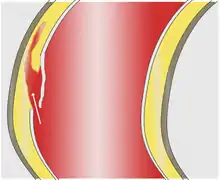

As with all other arteries, the aorta is made up of three layers, the intima, the media, and the adventitia. The intima is in direct contact with the blood inside the vessel, and mainly consists of a layer of endothelial cells on a basement membrane; the media contains connective and muscle tissue, and the vessel is protected on the outside by the adventitia, comprising connective tissue.[25]

In an aortic dissection, blood penetrates the intima and enters the media layer. The high pressure rips the tissue of the media apart along the laminated plane splitting the inner two-thirds and the outer one-third of the media apart.[26] This can propagate along the length of the aorta for a variable distance forward or backward. Dissections that propagate towards the iliac bifurcation (with the flow of blood) are called anterograde dissections and those that propagate towards the aortic root (opposite of the flow of blood) are called retrograde dissections. The initial tear is usually within 100 mm of the aortic valve, so a retrograde dissection can easily compromise the pericardium leading to a hemopericardium. Anterograde dissections may propagate all the way to the iliac bifurcation of the aorta, rupture the aortic wall, or recanalize into the intravascular lumen leading to a double-barrel aorta. The double-barrel aorta relieves the pressure of blood flow and reduces the risk of rupture. Rupture leads to hemorrhaging into a body cavity, and prognosis depends on the area of rupture. Retroperitoneal and pericardial ruptures are both possible.[27]

The initiating event in aortic dissection is a tear in the intimal lining of the aorta. Due to the high pressures in the aorta, blood enters the media at the point of the tear. The force of the blood entering the media causes the tear to extend. It may extend proximally (closer to the heart) or distally (away from the heart) or both. The blood travels through the media, creating a false lumen (the true lumen is the normal conduit of blood in the aorta). Separating the false lumen from the true lumen is a layer of intimal tissue known as the intimal flap.